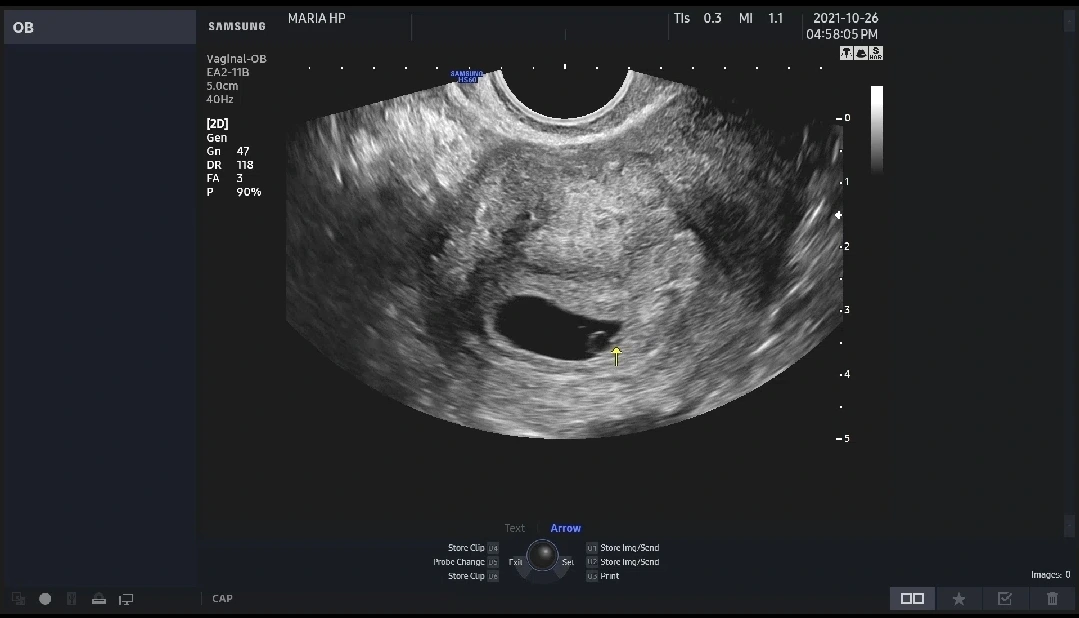

엄마의 마지막 생리일을 고려했을 때 석연치 않은 임신, 병원에서의 첫 반응도 엄마 아빠가 느꼈던 찜찜함과 다르지 않았어. 간호사 선생님은 진료 전 피검사부터 해보기를 제안하셨어. 피를 뽑고 초초하게 30분 정도 기다려 나온 결과는 '임신'. 인공수정과 시험관 시술을 수없이 반복하면서 그렇게 듣고 싶었던 임신이라 판단되는 피검사 수치가 나온 거야. 이어진 의신 선생님과의 초음파 진료에서도 아기집과 난황이 선명하게 보였어. 너의 모습은 아직 작고 작은 점에 불과했지만 우리에게 찾아와 준 너를 느끼기에 충분했어.